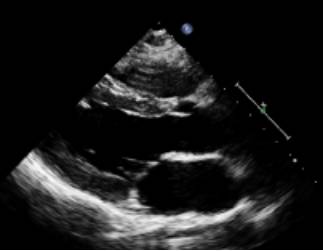

图|胸骨旁左心长轴切面,二尖瓣瓣尖水平。左图为舒张末期,右图为收缩末期。

随着图像处理技术的改进,已经提高心脏结构的分辨率。可按照真实的组织和血流的界面来测量室间隔和左心室后壁的厚度,而不是像以前测量前缘回声之间的距离。

ASE推荐于二尖瓣瓣尖水平胸骨旁短轴切面直接测量或采用M型曲线测量。M-型超声时间分辨率好。有助于帮助二维超声区分临近左室后壁的肌小梁、室间隔左室面的假腱索、室间隔右室面的调节束等结构。即使采用二维引导也可能无法保证M-型取样线完全垂直于室间隔和左心室后壁。